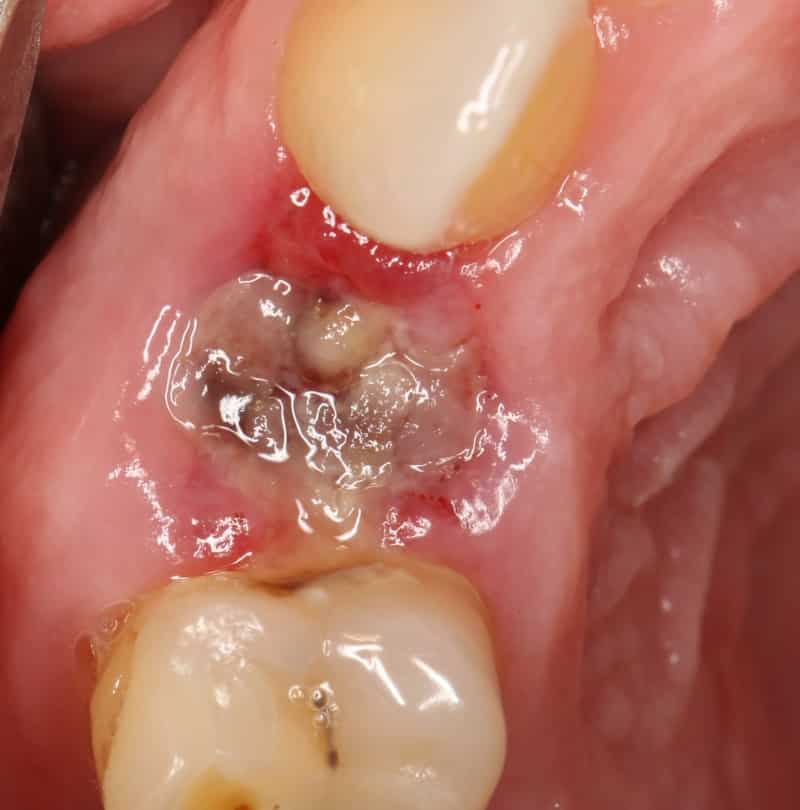

В течение 2-3 дней сгусток меняет цвет, постепенно светлея и образуя каркас из фибрина, который является основным компонентом тромба. Тромб продолжает защищать лунку от инфекции и предотвращает кровотечение из десны. Для нормального заживления раны важно не трогать её и избегать раздражения.

Примерно через 4-5 дней открытая рана в лунке начинает заживать грануляционной тканью, а сгусток крови всасывается в слизистую десны, что свидетельствует о почти полном заживлении и начале формирования новой костной ткани, процесс которого займет несколько недель. В этот период вы можете заметить, что цвет десны становится более светлым и желтоватым. При отсутствии других негативных симптомов это будет нормальным явлением, связанным с выделением фибрина из крови.

Важно помнить, что при ослабленном иммунитете даже простое удаление зуба может значительно увеличить риск заражения лунки альвеолитом. Последствия этого можно увидеть на фотографиях гноя в лунке после удаления зуба.